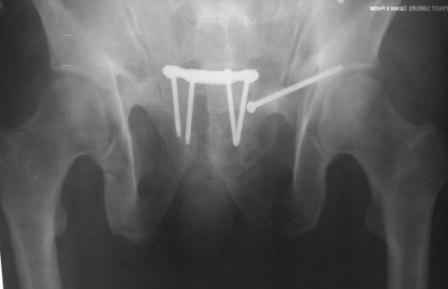

Уважаемый Ерсин Жунусов,

положение и точка введения винта, при фиксации перелома горизонтальной ветви лонной кости и возможно acetabulum, определяется её анатомией. Корректная позиция и точка введения в приложенных картинках из руководства по внутреннему остеосинтезу.

С Уважением А.Миронов

1.jpg

64KB (66029 bytes)